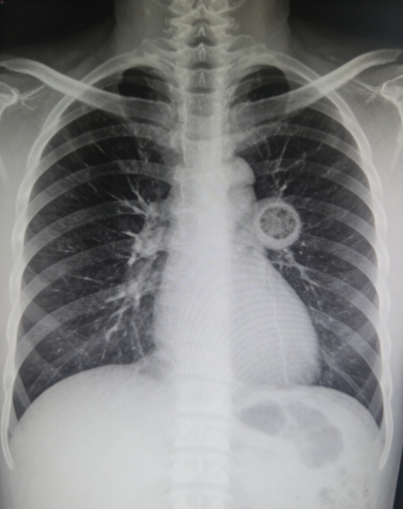

肺磨玻璃结节在CT影像上就像一小片模糊的磨砂玻璃,它可能是炎症,也可能是早期肺癌的信号。尤其是那些在随访中逐渐增大、内部实性成分增多的结节,需要引起高度重视。过去,外科手术切除是主要手段,但对于高龄、肺功能差、或结节多发的患者,手术创伤大、会损失较多正常肺组织。

医生仅用1-2毫米粗的消融针,经皮肤穿刺,在CT影像的实时“导航”下,准确刺入结节中心。随后,针尖释放高频微波,使结节局部瞬间产生60-120℃的高温,让病变细胞发生不可逆的凝固性坏死,相当于用高温将其原位“灭活”。术后,坏死组织会逐渐被人体吸收,而周围的健康肺组织得以完整保留。